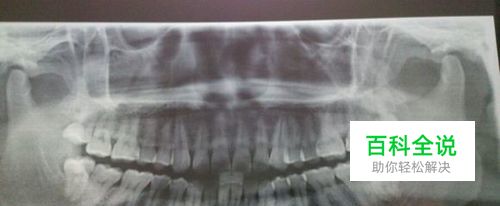

护士会叫你的名字然后让你去找你的主治医生,医生会看看你的牙齿情况给你一些拔牙的建议,给我看牙的那位医生让我拔右侧的上下两颗牙,但是我没有听劝,就拔掉了下面的一颗智齿。费用大概快到六百块钱。我去的那个医院是只收现金或者刷卡的,所以你要去的话,最好带上银行卡或者足够的现金。然后去拍片子,抽血。 我去的那个口腔医院,拍片子和抽血都在一楼,跟着人流走就对啦。